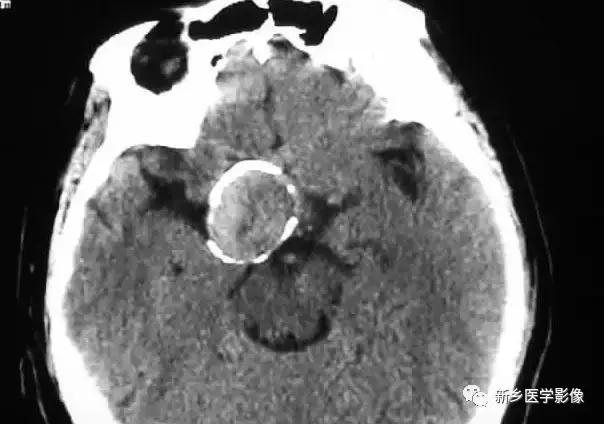

四、脑包虫病

以在脑实质里形成巨大囊肿为特征,囊壁可出现壳状钙化完整或不完整,或囊壁出现结节样钙化,囊壁钙化的出现有助于与囊壁无钙化的颅内囊性病变区别,如神经上皮囊肿、蛛网膜囊肿。